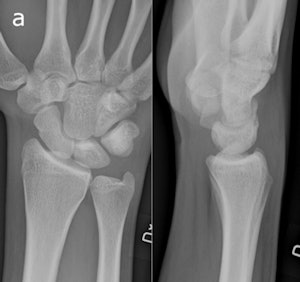

In the study, digital radiography was performed in the emergency department on 36 consecutive patients at the time of injury with pixel spacing of 0.1 mm. Posteroanterior (PA) and lateral views were captured. Coned-down special scaphoid views were obtained with the hand in ulnar deviation and the wrist in a slight pronation and supination, respectively, to obtain views of the proximal and distal half of the scaphoid with the x-rays perpendicular to the long axis of the bone.

The CR protocol was identical to the previous ER imaging routine. For tomosynthesis, 60 low-dose projection images were used to reconstruct tomographic sections with 1-mm nominal thickness without overlap, with a pixel spacing of 0.2 mm. The detector was stationary, while the x-ray tube was moved continuously from -17.5° to +17.5° around the standard PA position.

The experience also taught the participating radiologists that detecting fractures with tomosynthesis is somewhat different than with conventional radiography and CT. Fracture detection is mainly based on edge disruption with tomosynthesis because the structure of the medullary bone is blurred and not as distinct as in CT, Geijer noted.

The tomosynthesis sections had a "nonprecise" thickness, with a sharp resolution at the image center, and increasing "fuzziness" apparent toward the image edges.

Fracture detection was aided on the lateral borders by the ability to visualize the scaphoid bone cortex. Fractures could also be appreciated on the most dorsal and palmar sections because of good contrast between the bone and surrounding soft tissue or medullary bone, he wrote.

Image artifacts with tomosynthesis included increased noise during scaphoid imaging and the superimposition of adjacent cortical lines and carpal joint structures.

"The way a fracture is seen with tomosynthesis is thus different from both radiography and CT," he wrote.